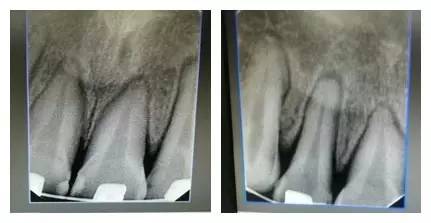

檢查:上前牙松(Ⅱ)°,牙齦紅腫,牙周膜間隙增寬。(如照片所示)

1.jpg